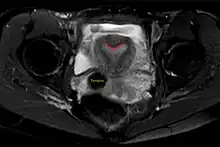

| Arcuate uterus (marked in red) seen on MRI | |

The arcuate uterus is a form of a uterine anomaly or variation where the uterine cavity displays a concave contour towards the fundus. Normally the uterine cavity is straight or convex towards the fundus on anterior-posterior imaging, but in the arcuate uterus the myometrium of the fundus dips into the cavity and may form a small septation. The distinction between an arcuate uterus and a septate uterus is not standardized.

Helpful techniques to investigate the uterine structure are transvaginal ultrasonography and sonohysterography, hysterosalpingography, MRI, and hysteroscopy. More recently 3-D ultrasonography has been advocated as an excellent non-invasive method to delineate the condition.[5]